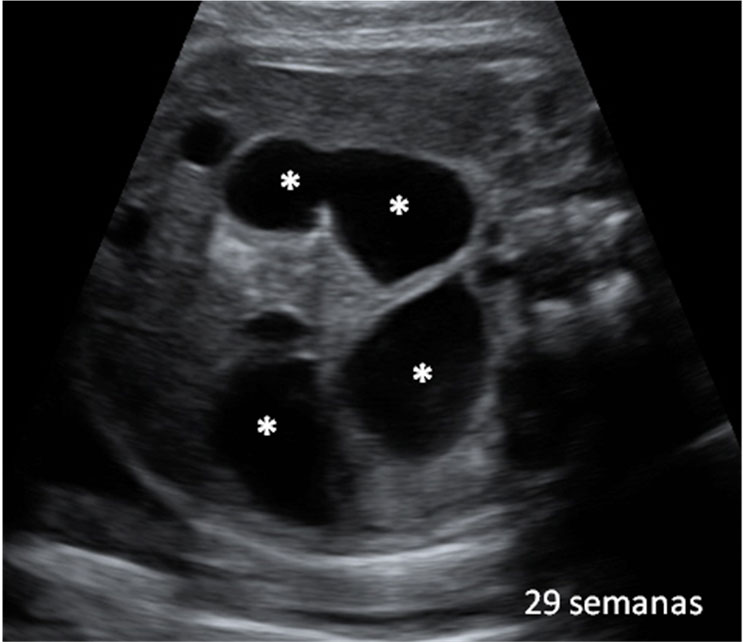

En la semana 20 de gestación, la ecografía en 2D muestra los genitales de un feto varón ya formados, aunque los testículos aún se encuentran alojados dentro de la cavidad abdominal. En unas semanas descenderán hasta las bolsas escrotales.